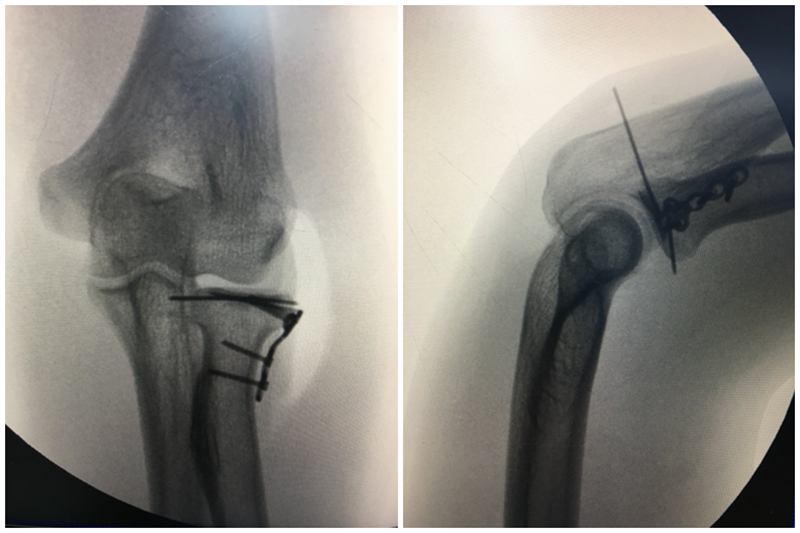

图7 桡骨头2型 赤道半球骨折

图8 EDC入路切口

图9 骨折固定